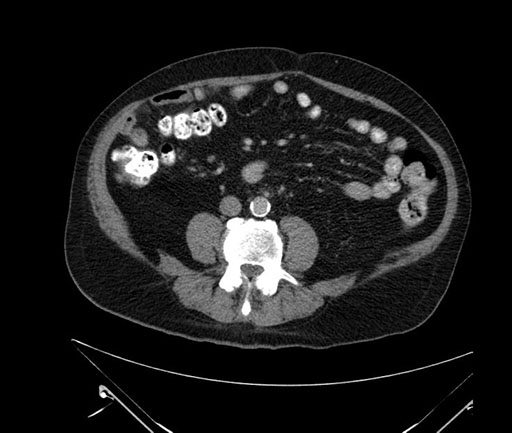

Imaging Analysis

Look through the patient's CT scan to identify any areas of concern for the necessary procedure.

Based on your CT findings, which issue(s) would give reason for "planned slowing down moment(s)" in this case?